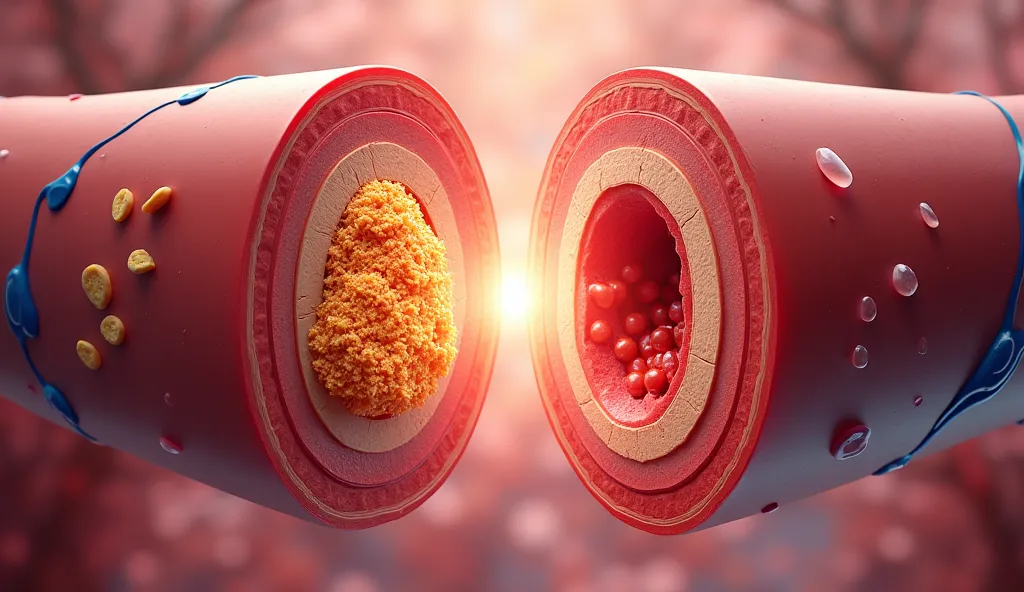

Create a drawing where it is two shoulders, one with. Low thermometer and the ot

Create a drawing where it is two shoulders, one with. Low thermometer and the other with the high thermometer , is to reflect the real numbers

Create a drawing where it is two shoulders

Low thermometer and the other with the high thermometer

is to reflect the real numbers